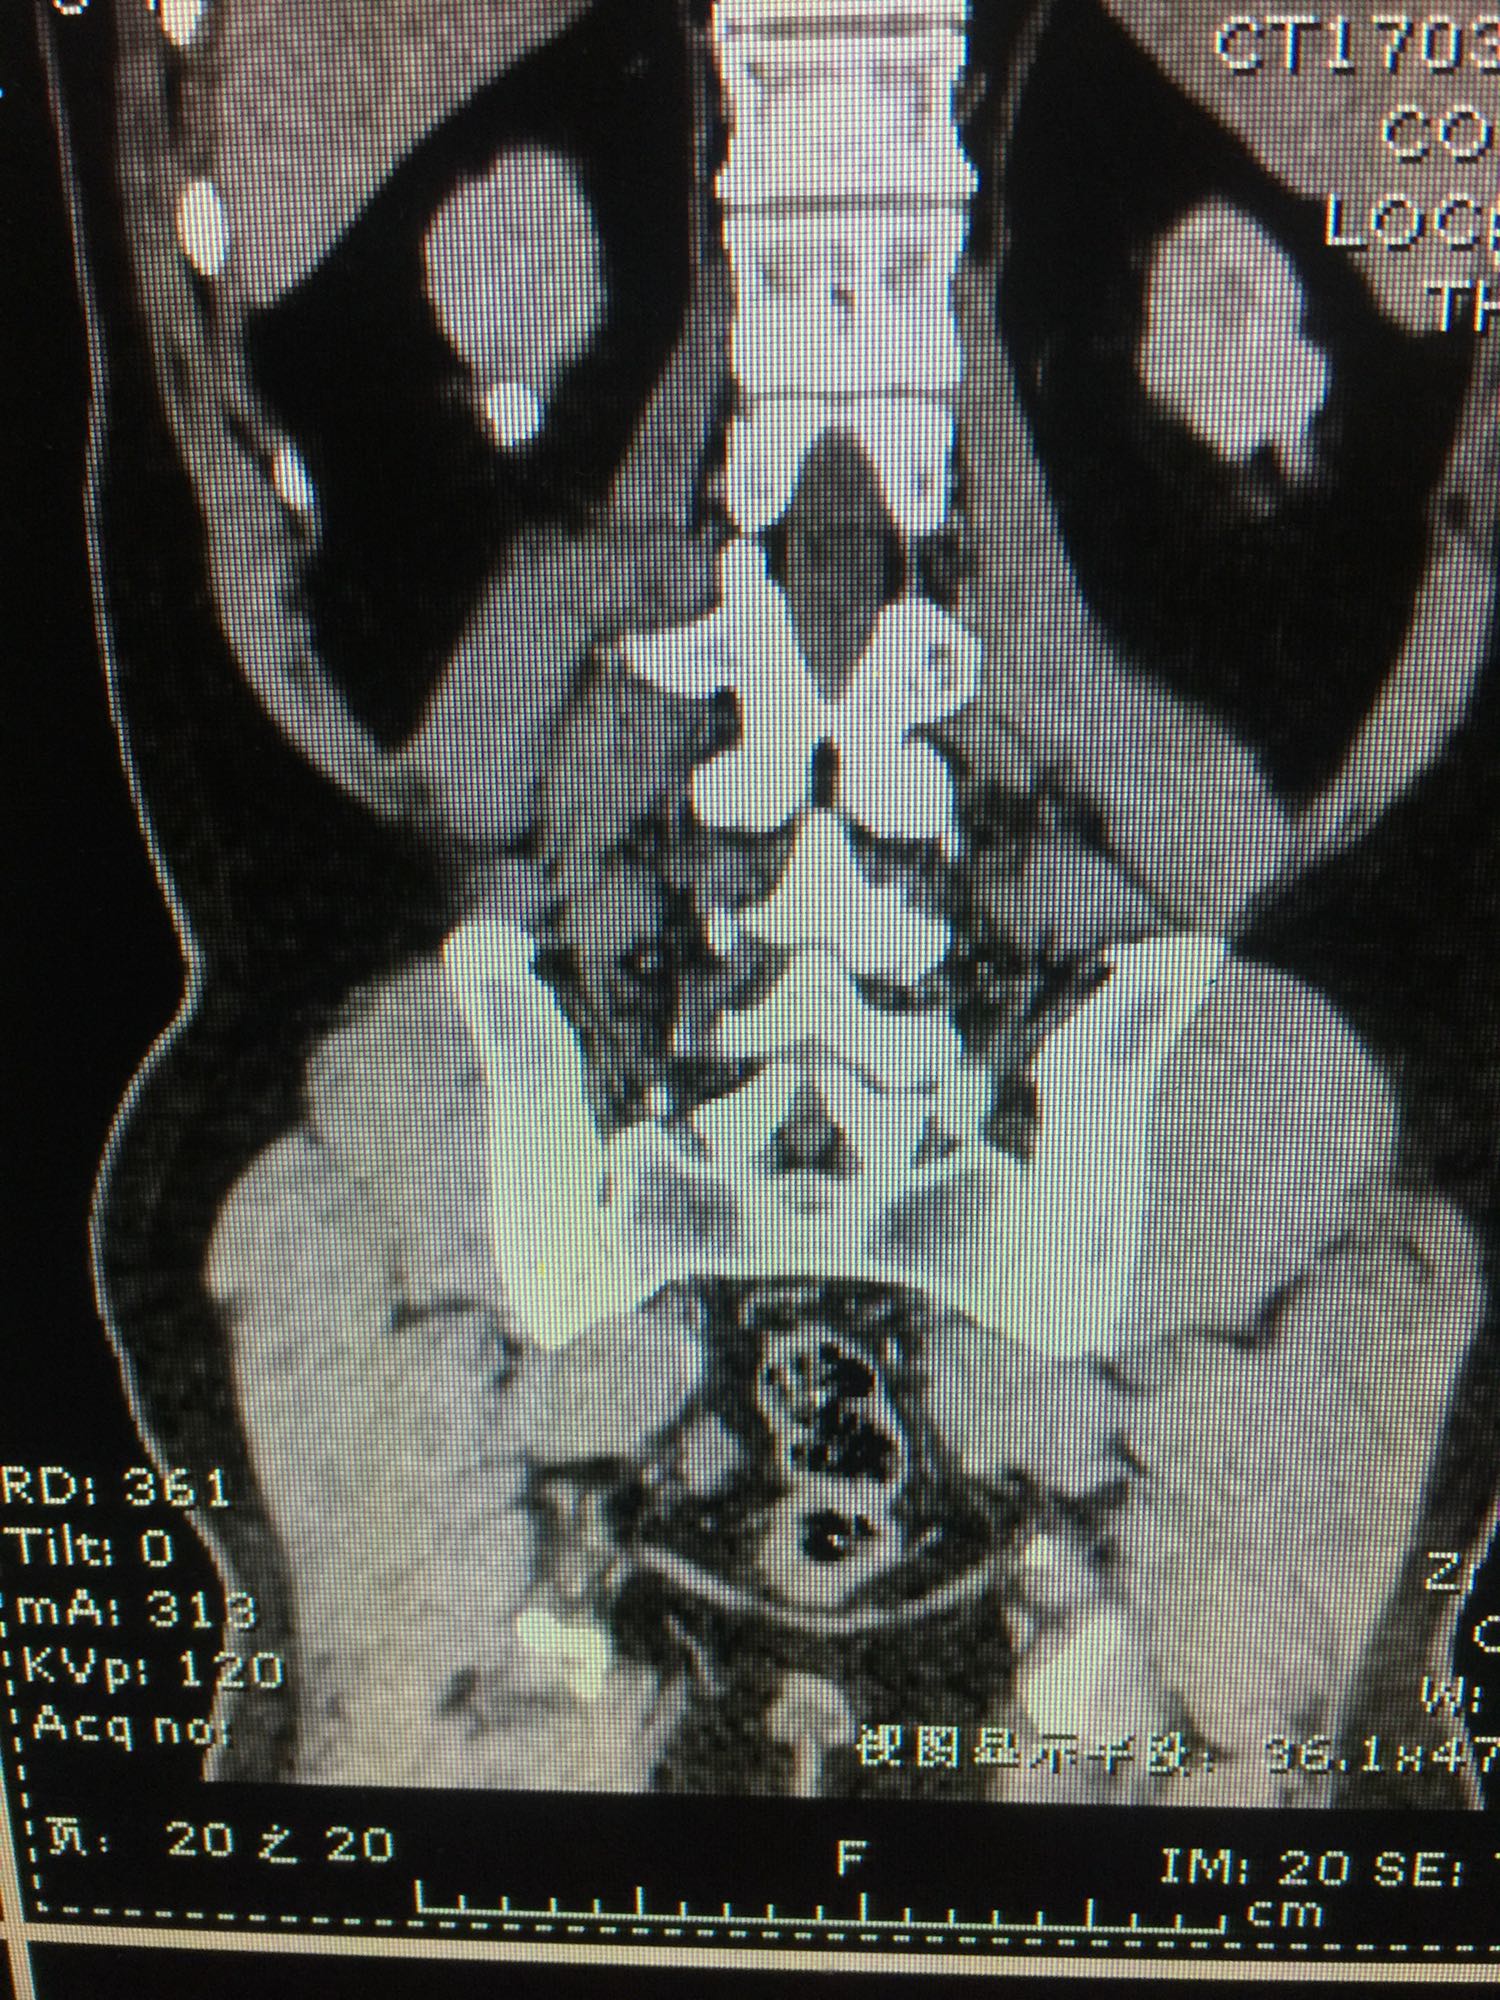

查体:双肾区无叩压痛,膀胱区无叩压痛,无叩浊,前列腺二度,质地中等,无压痛,无结节。CTU提示右肾铸型结石。ECTL 40,R14.5

右肾铸型结石 予以经皮肾碎石治疗,术后复查平片未见结石残留。

铸型结石以经皮肾手术作为主要的术式。但手术可能一次或多次进行。术后残留结石,术后复发等几率高。我们见过2月后几乎又长满的结石。